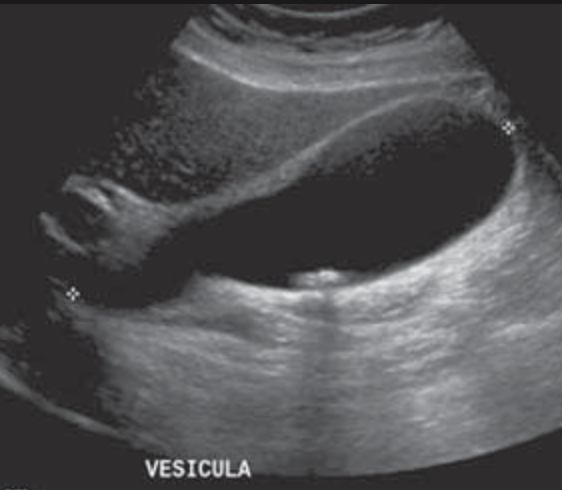

2. US Vías biliares

1. Signo Murphy, engrosamiento pared >4mm, distensión VB >8cm largo, >4cm corto, lito impactado en cuello, liq. perivesicular